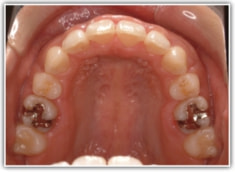

上顎前突ケース

治療法:表の矯正(T21ブラケット)

治療前